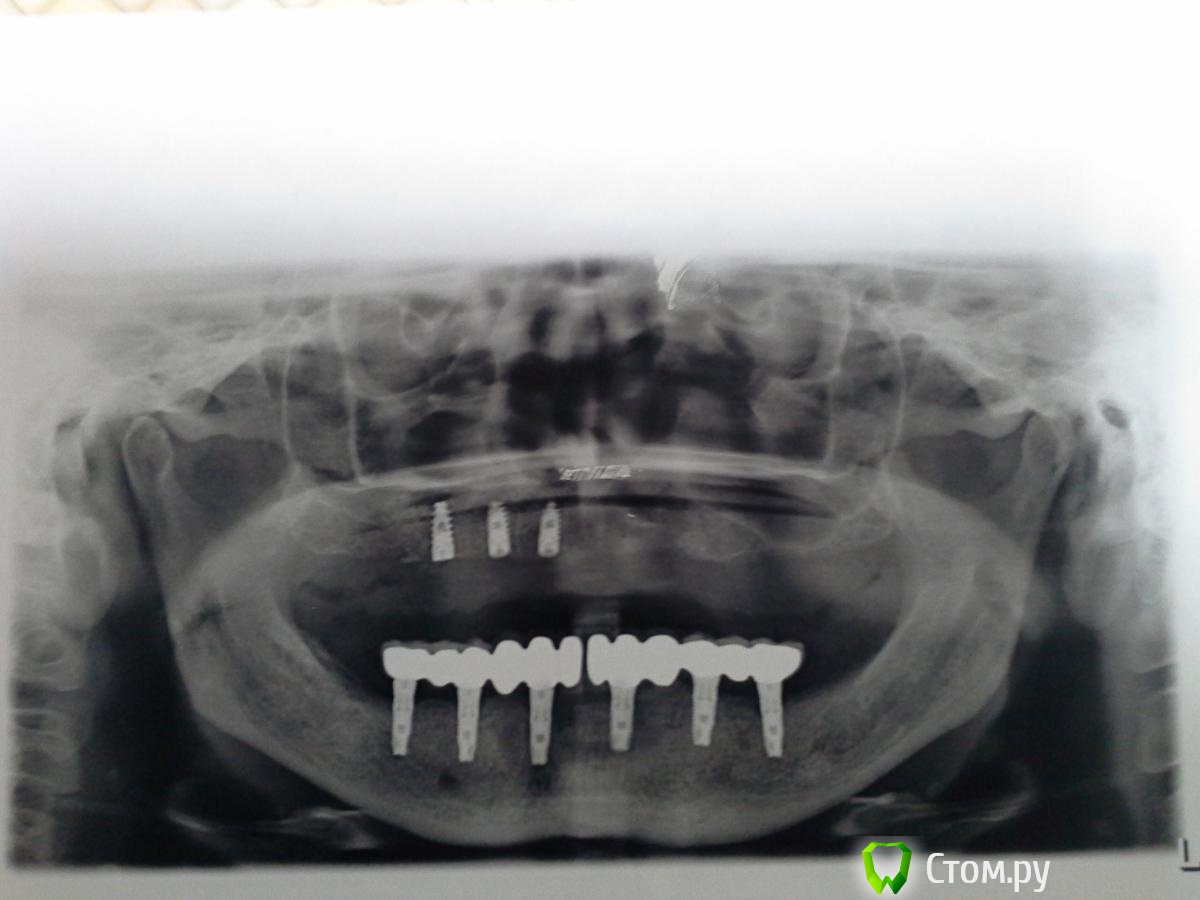

Magomed Опубликовано 3 сентября, 2014 Поделиться Опубликовано 3 сентября, 2014 (изменено) работу делал год. в.ч.удалил 8 з. низ 6 з. в.ч. каркас фрезеров. низ литьё. Изменено 3 сентября, 2014 пользователем Magomed Ссылка на комментарий

anvladd Опубликовано 4 сентября, 2014 Поделиться Опубликовано 4 сентября, 2014 смущают консоли на верху. Ссылка на комментарий

Bier Опубликовано 4 сентября, 2014 Поделиться Опубликовано 4 сентября, 2014 смущают консоли на верху.чем? есть же формула, уверен они вписываются в нее. Ссылка на комментарий

ILGAMSA Опубликовано 4 сентября, 2014 Поделиться Опубликовано 4 сентября, 2014 смущают консоли на верху.По ITI если протяженность протяженность конструкции не менее 30мм, то длина консоли может достигать... внимание(!)... 15мм! 1 Ссылка на комментарий

Bier Опубликовано 4 сентября, 2014 Поделиться Опубликовано 4 сентября, 2014 влияет не количество опор, а передне-задний размер. между передним и задним имплантатом. 1 Ссылка на комментарий